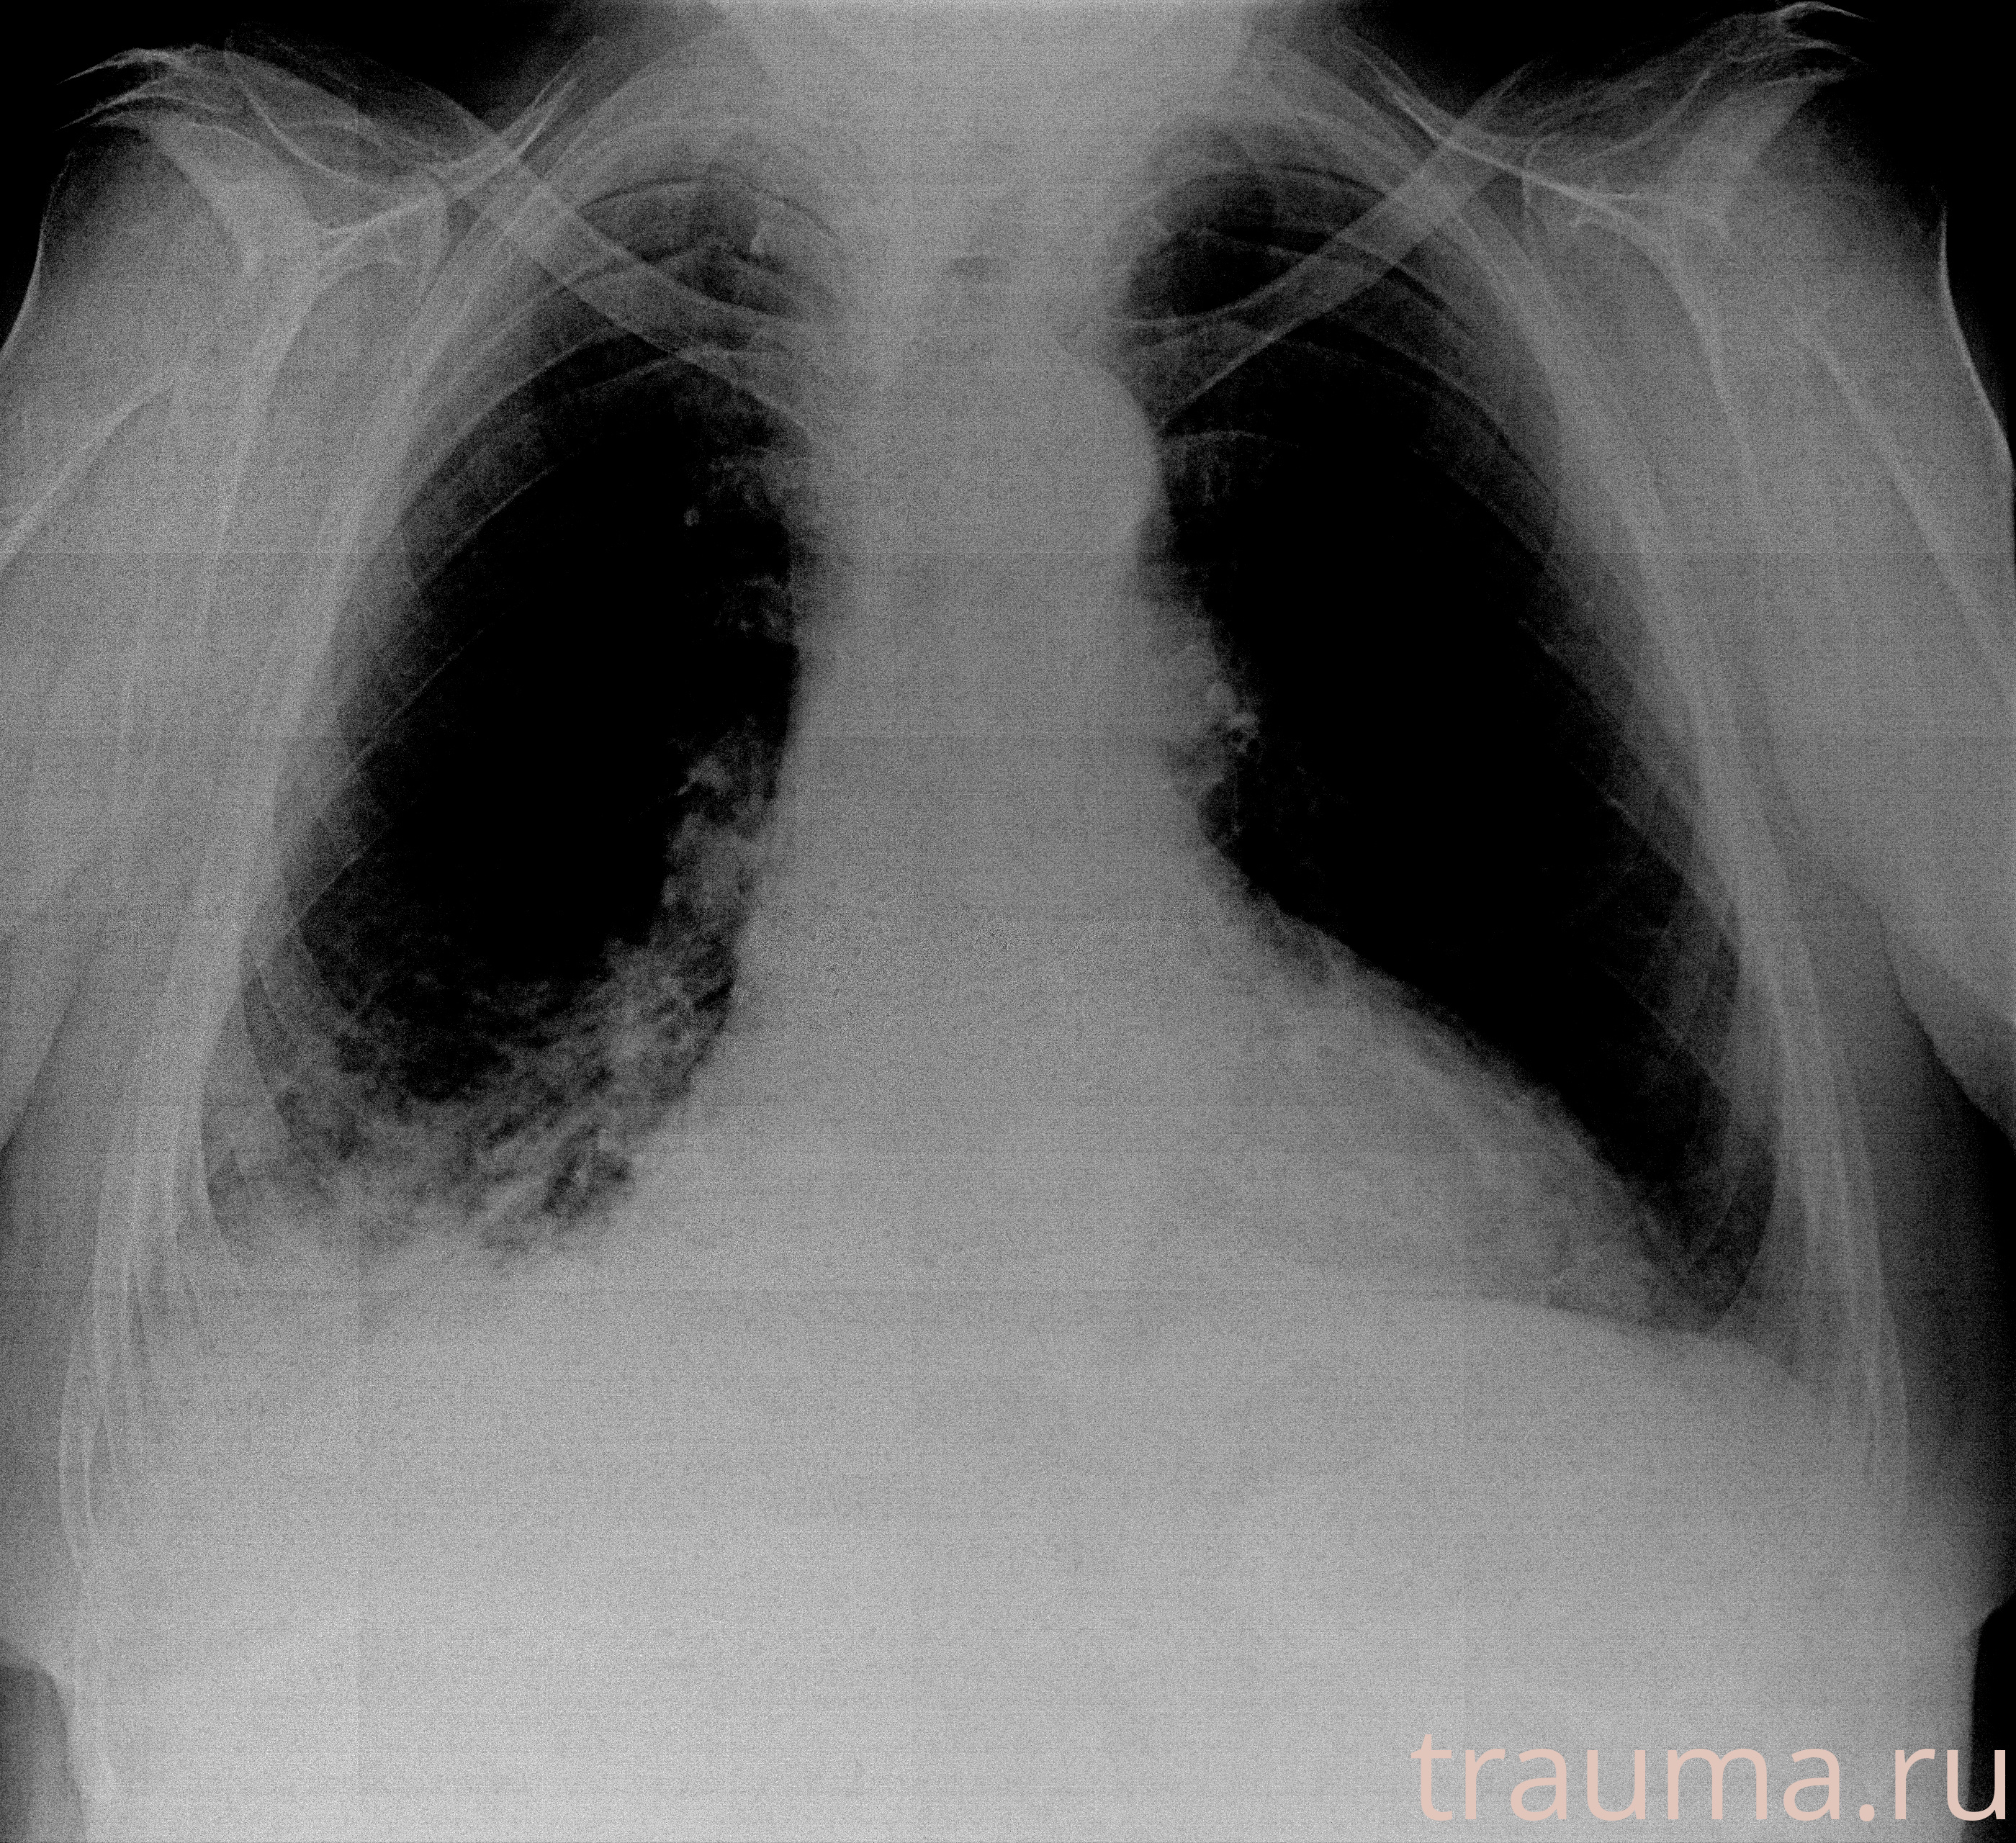

Рентгенограммы

Рентген на дому: по вашему адресу приезжает врач-рентгенолог, травматолог-ортопед с мобильным рентгеновским аппаратом, проводит диагностику травмы или заболевания, делает необходимые рентгенограммы, дает рекомендации по дальнейшему лечению. Получить качественные снимки в домашних условиях возможно благодаря уникальной методике, разработанной МосРентген Центром для института  Склифосовского

при переломе шейки бедра и пневмонии от компании МосРентген Центр - партнера Института имени Склифосовского